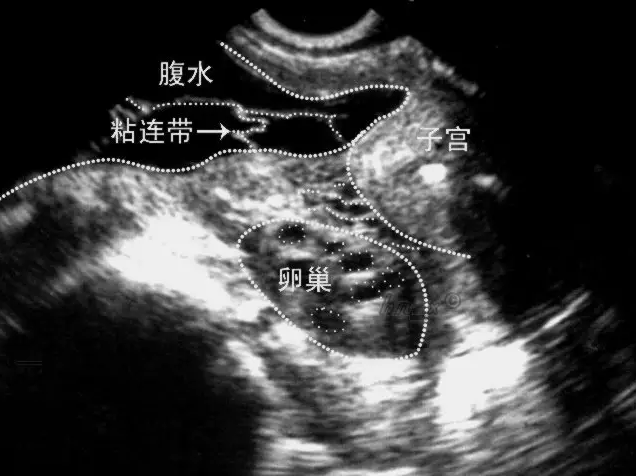

很多女性朋友來(lái)到醫(yī)院監(jiān)測(cè)卵泡,排卵正常,但總是懷不上,偶有小腹下墜感覺(jué),這種情況,您需要引起重視!因?yàn)槟赡芑加信枨徽尺B!

盆腔黏連主要是指盆腔內(nèi)的組織出現(xiàn)了細(xì)菌感染或者病毒感染,從而導(dǎo)致組織器官出現(xiàn)了炎癥的現(xiàn)象,由于盆腔黏連的出現(xiàn),很有可能會(huì)導(dǎo)致患者出現(xiàn)子宮輸卵管炎,卵巢炎等等問(wèn)題,由于這些疾病的原因,就有可能會(huì)導(dǎo)致患者的身體癥狀出現(xiàn),比如患者可能會(huì)出現(xiàn)水腫,分泌物增多等等問(wèn)題,如果不及時(shí)的進(jìn)行控制,還有可能會(huì)誘發(fā)其他問(wèn)題的出現(xiàn),如影響輸卵管蠕動(dòng)和絨毛擺動(dòng),無(wú)法正常拾卵,影響女性懷孕。